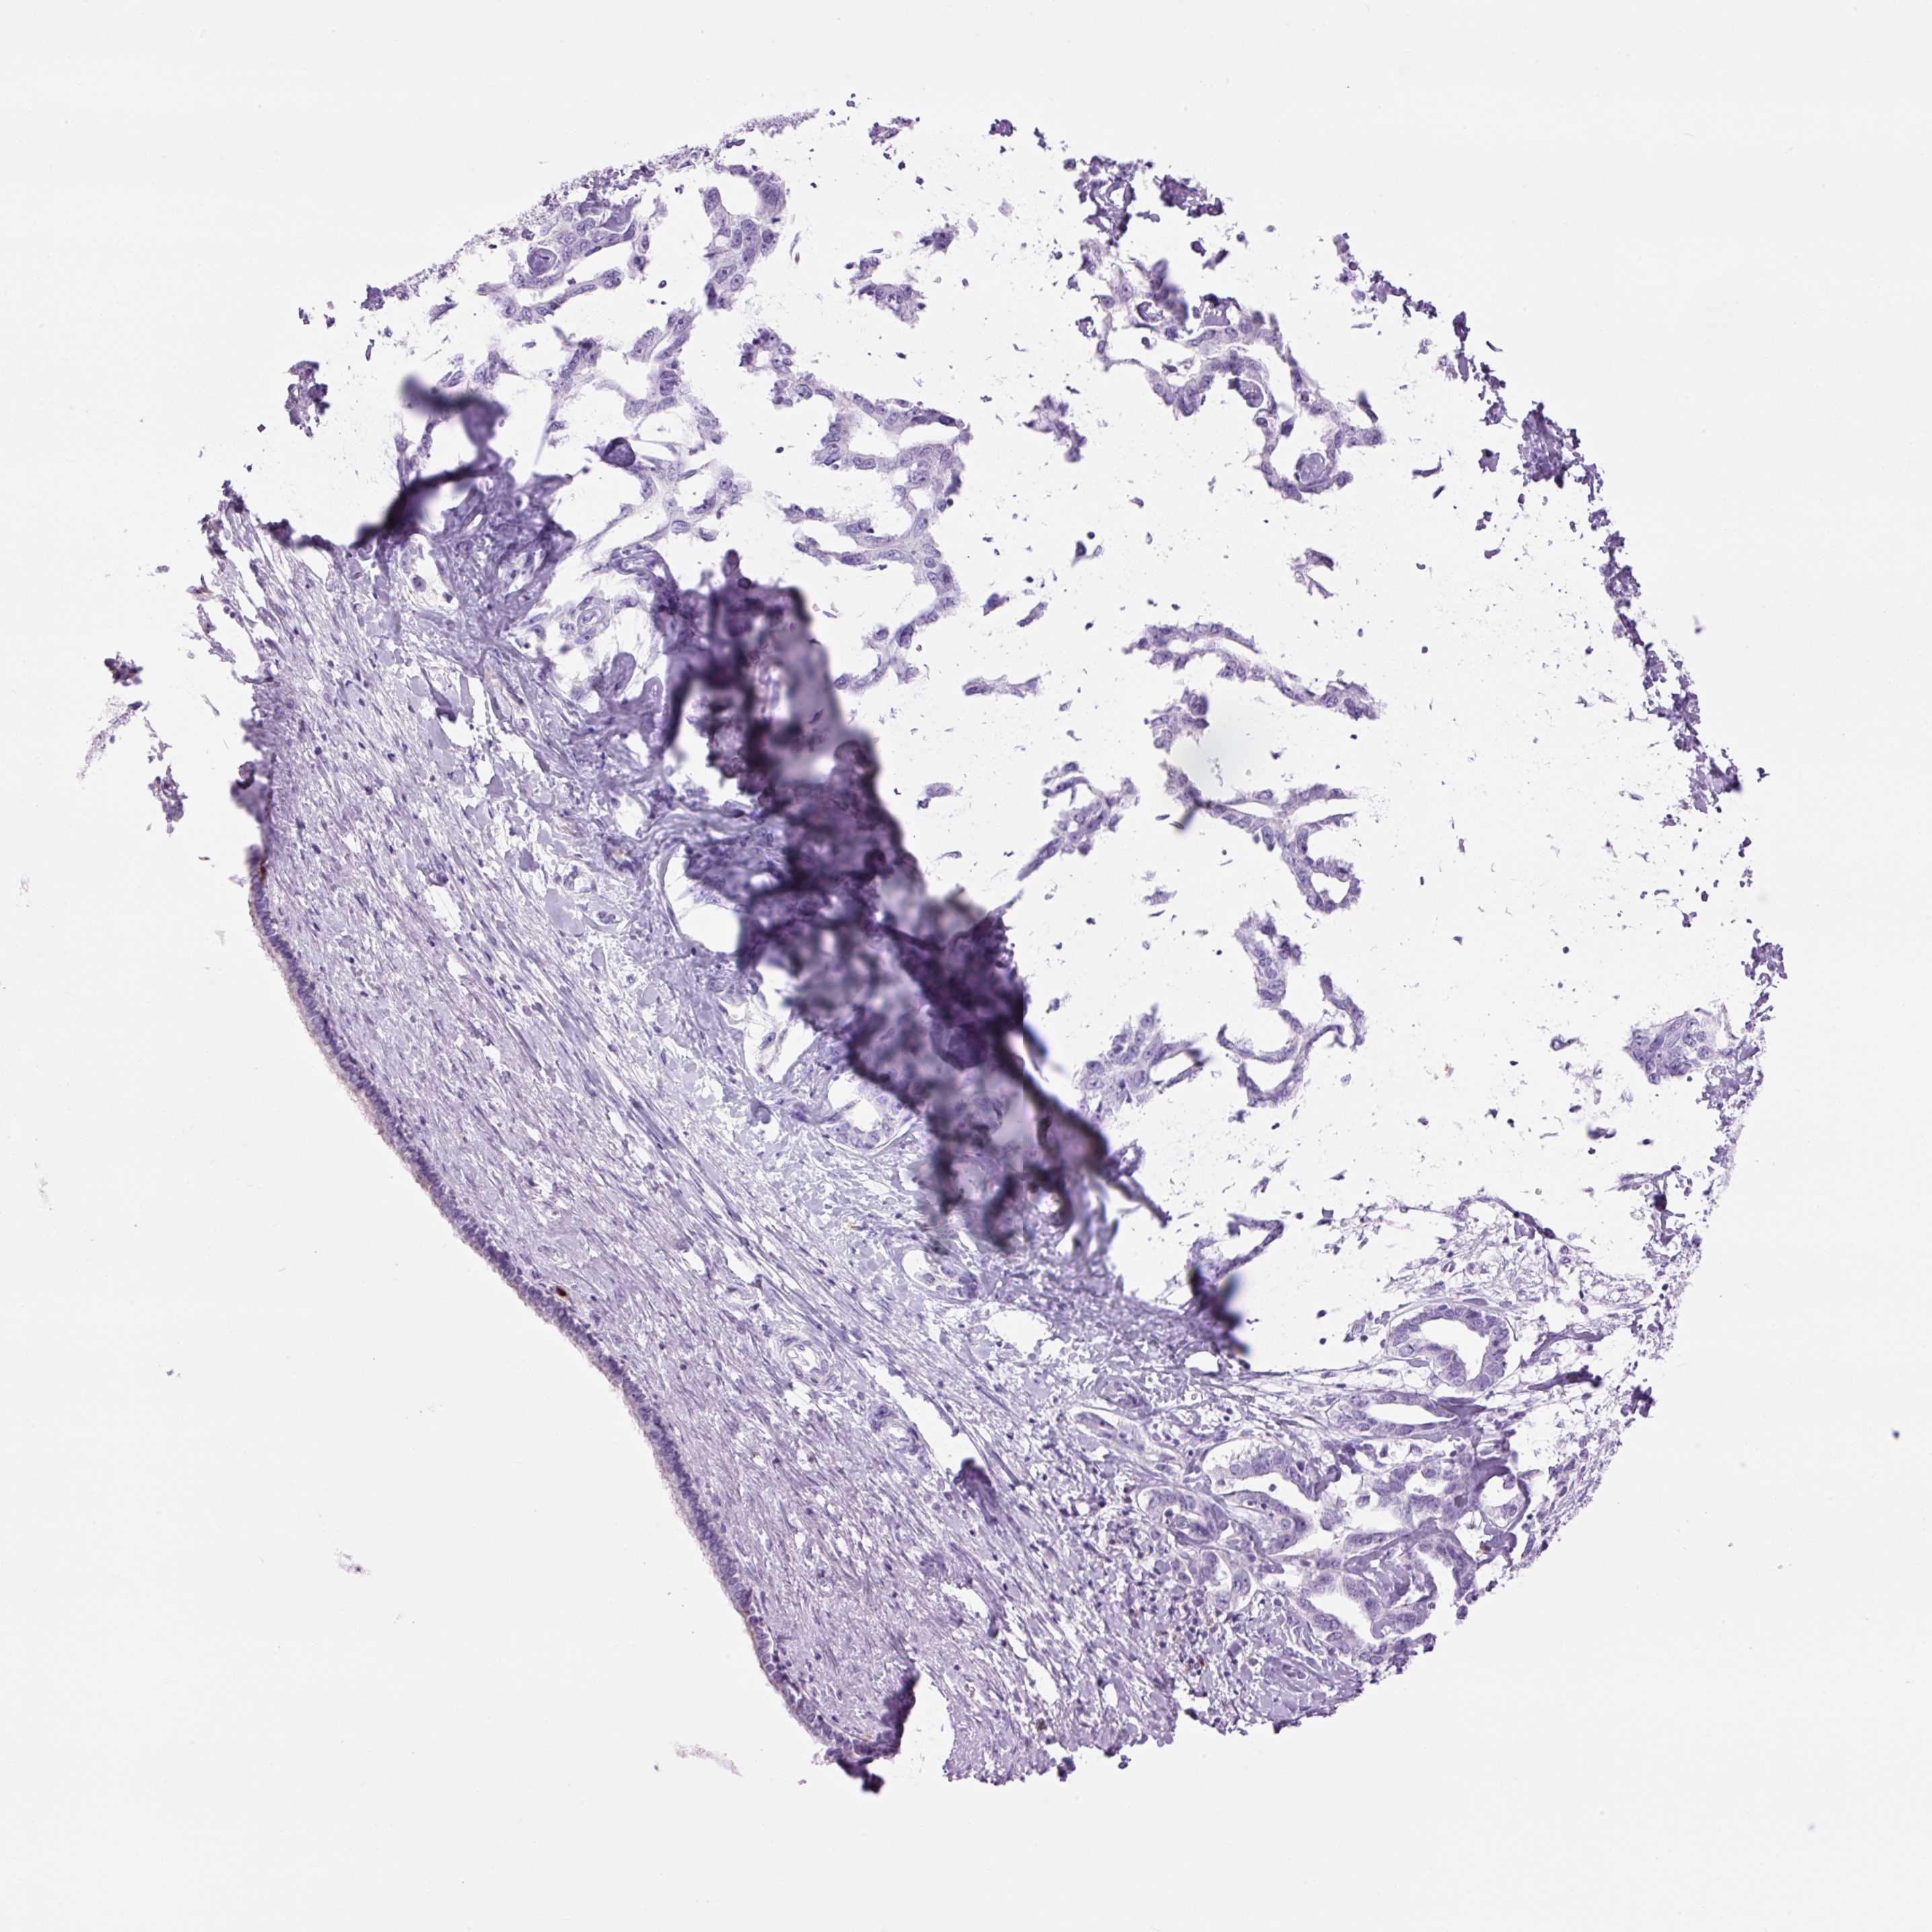

LIVER CANCER - Protein expressioni

A mouse-over function shows sample information and annotation data. Click on an image to view it in a full screen mode. Samples can be filtered based on level of antibody staining by selecting one or several of the following categories: high, medium, low and not detected. The assay and annotation is described here.

Note that samples used for immunohistochemistry by the Human Protein Atlas do not correspond to samples in the TCGA dataset.

Antibody stainingi

Antibody staining in the annotated cell types in the current human tissue is reported as not detected, low, medium, or high, based on conventional immunohistochemistry profiling in selected tissues. This score is based on the combination of the staining intensity and fraction of stained cells.

Each image is clickable and will lead to virtual microscopy that enables deeper exploration of all samples and also displays staining intensity scores, fraction scores and subcellular localization as well as patient and tissue information for each sample.

Cholangiocarcinoma

Carcinoma, Hepatocellular, NOS

Carcinoma, metastatic, NOS